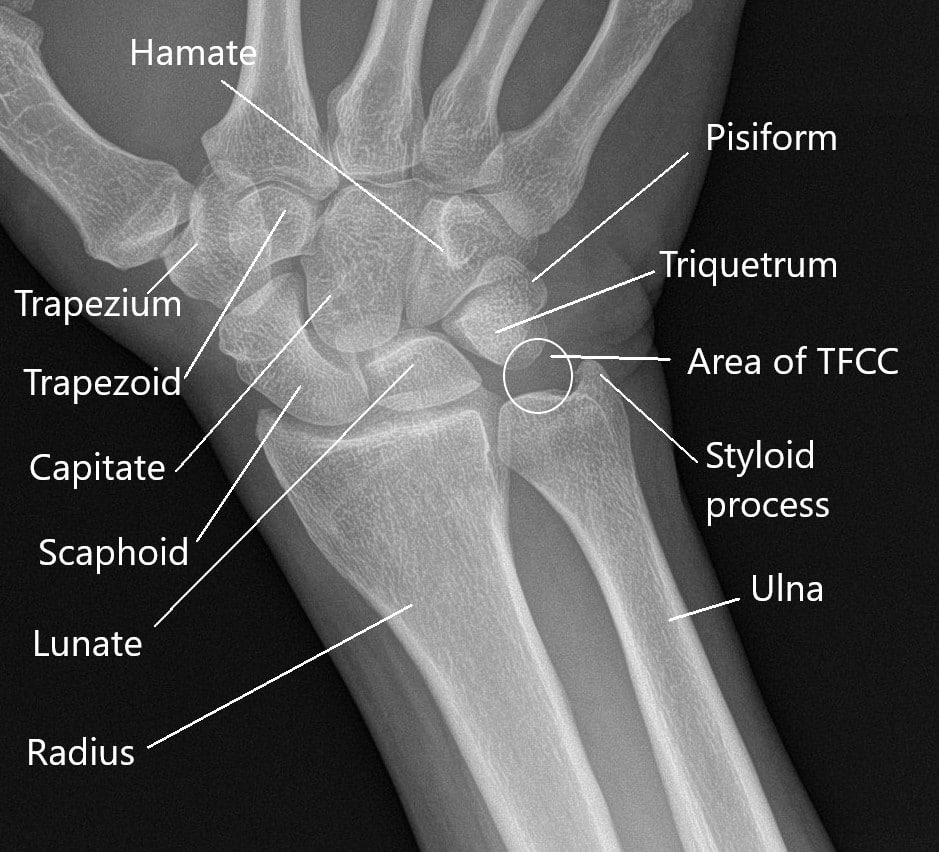

x ray of right hand and wrist

Posts: x ray of right hand and wrist